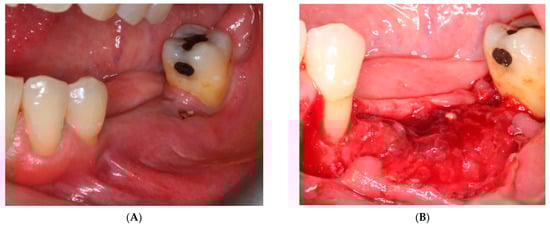

- First surgery: Local anesthesia Articaine 4% with epinephrine (1:100,000) was administered. An intrasulcular incision was made from the mesial of 3.3 to the distal of 3.7, continuing along the anterior border of the external ramus of the mandible. Periosteal incisions were made to mobilize the vestibular flap and the upper fibers of the mylohyoid muscle were disinserted to passivate the lingual flap and thus obtain a tension-free closure (Figure 3). We then checked the position of the mesh and proceeded to collect bone from the ascending branch using the bone scraper (Micross®, Selecdent, Barcelona, Spain) (Figure 4A). Cortical perforations were made to promote bleeding (Figure 4B). We mixed the autologous bone with the xenograft (Tioss®, Sanhigia, Bujaraloz, Spain) in a 70:30 ratio, inserted it into the mesh, and the mesh was placed in the defect.

- On the day of surgery, the titanium mesh and the microscrews were removed (Figure 9). When the mesh was removed, a soft consistency was observed in the most coronally newly formed bone and it was decided to postpone the placement of the implants and allow it to ossify for another month and a half. A panoramic radiograph was taken after surgery (Figure 10).